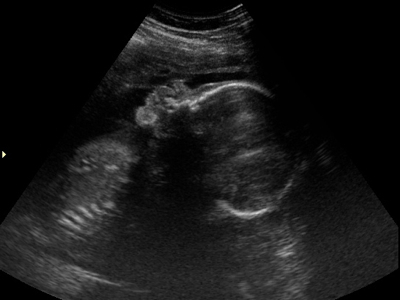

Tuesday was a 28-week ultrasound for #3 (we’ll reveal the puzzle solution with his name soon!). Thankfully it went much better than Dora’s did. He was in a good position for us to measure his growth as well as see his cute little face!

After two pregnancies that defied all the odds, it’s a relief to be “just” average. At the appointment we discovered that #3 is in the 56th percentile for growth, already weighing approximately 2 lbs. 12 oz.! That means he’s right in the middle of typical—a good thing, since James was in the 1st percentile and weighed 2 lbs. 14 oz. when he was born at 35 weeks.

And what do you think—does he look like James or not? The first two pics are #3, and the last two are James a week younger:

Yes, they sure do look like brothers.

my first thought was that #3 doesn’t look like James, but after seeing J’s ultrasound, I’m thinking their nose is alike.

They’re both adorable. They do look alike but it looks like #3 has a super cute little nose.

I definitely see a resemblance to James. Not so much comparing them in the ultrasounds, but the second ultrasound of Number Three, where you can see his face straight-on, he looks like several of the pictures that were posted of James. 🙂